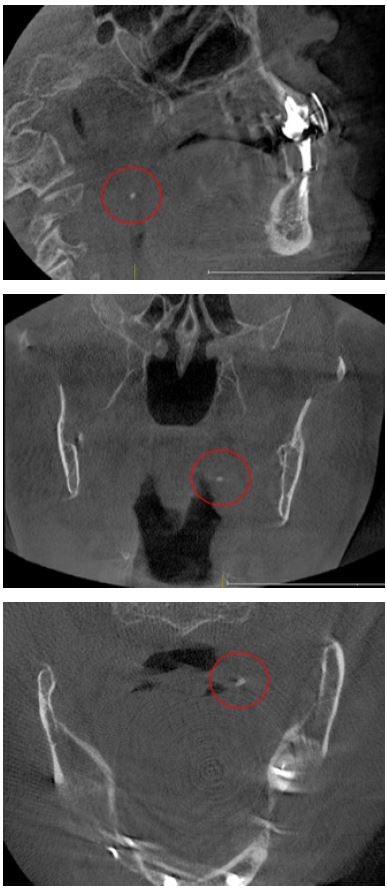

Los tonsilolitos encontrados afectaron, principalmente, a las amígdalas palatinas (figura 1), con un 96,8 % (n = 120); a las amígdalas linguales (figura 2), con un 2,4 % (n = 3); y, finalmente, a las amígdalas nasofaríngeas (figura 3), con un 0,8 % (n = 1) (tabla 10).

Imágenes tomadas del archivo del Servicio de Radiología Bucal y Maxilofacial del CDD-UPCH

Los tonsilolitos fueron encontrados principalmente en la amígdala palatina, en un 96,77 % (n = 120); seguido de la amígdala lingual, en un 2,42 % (n = 3); de las amígdalas nasofaríngeas, 0,81% (n = 1); y finalmente no se encontraron tonsilolitos en las amígdalas tubáricas. Ello coincide con distintos informes (8,10,11), que muestran que los tonsilolitos palatinos son uno de los hallazgos más comunes entre las calcificaciones patológicas en la región de la cabeza y el cuello, oscilando entre el 16 % y el 46,1 %. La alta prevalencia de tonsilolitos en las amígdalas palatinas podría deberse a que estas presentan criptas más profundas, ramificadas y relativamente apretadas. Las amígdalas linguales presentan criptas poco aplanadas, poco ramificadas, bastante separadas unas de otras. Las amígdalas faríngeas y tubáricas no presentan criptas típicas sino pliegues con recesos irregulares. Además, las amígdalas palatinas suelen estar más expuestas a las infecciones crónicas recurrentes, al tabaquismo, a las bebidas alcohólicas y a la mala higiene en comparación con las amígdalas linguales nasofaríngeas (12,15).